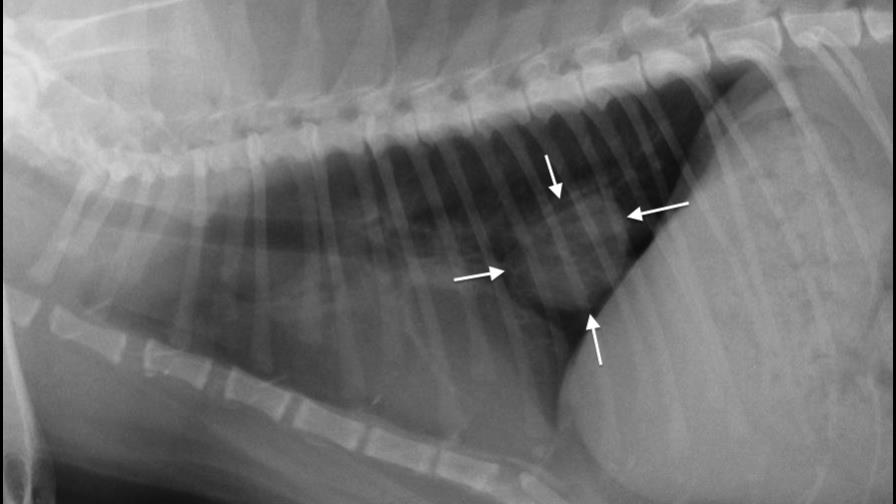

El humo de segunda mano puede causar cáncer pulmonar y nasal en los perros, linfoma maligno en los gatos y alergia y problemas respiratorios en ambos animales, según estudios en la Escuela de Medicina Veterinaria en la Universidad Tufts en Massachusetts, la Universidad Estatal de Colorado y otros establecimientos.

No se conoce el número de mascotas que muere cada año, pero los veterinarios saben, gracias a pruebas de laboratorio y visitas a sus consultorios, que la inhalación de humo causa reacciones alérgicas, inflamación y cáncer nasal y pulmonar en los animales domésticos, dijo Kerri Marshall, directora de veterinaria de Trupanion, empresa de seguros para mascotas.